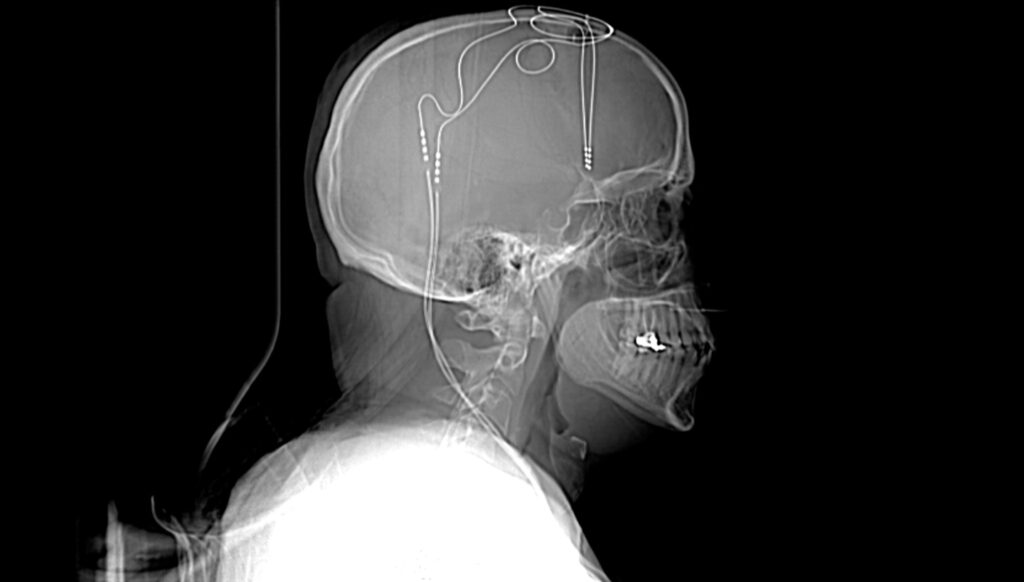

Amanda: My initial response was a little bit of skepticism, like, “OK, we’re gonna put a box in you, we’re gonna hook it up to some wires, we’re gonna shove them down in your brain and then electrocute you, and it’s gonna make you feel great.” Like, this doesn’t seem like a, like a safe thing to be doing.

Helen Mayberg: And so it was pretty surprising when we get to the third contact, and we start to turn it up, and we get to about 5 volts. It’s like it goes from 0 to 10. And all of a sudden, the patient goes, “Oh, that’s interesting. The void is gone.” I, I don’t even know how to explain it. I can’t speak for anybody else. There’s a moment where you’re just not even sure what you’ve just watched happen.